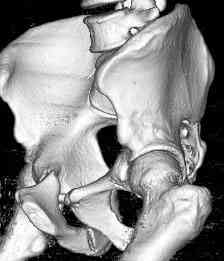

Уважаемые коллеги! опять вопрос по повреждению таза. Больной получил производственную травму 10 дней назад - удар балкой около 3 тонн в область верхней трети правого бедра и лона.

Был диагностирован перелом "типа бабочки" и повреждение уретры. Сделана цистостома. У насв отделении 3 дня. Имеется огромная флюктуирующая гематома с "галифе"-образной деформацией обеих бедер. Пнкционно эвакуировали в несколько приемов из подфасциальных полостей на бедрах около 3 литров геморрагического отделяемого с последующей эластической компрессией. При пункциях выявлено сообщение полостей на бедрах - видимо через поравннуюдиафрагму дна и полость таза - при удалении крови справа уменьшался объем левого бедра. Какой то активности проявялять покабоимся - аппаратная фиксация через отслоенные ткани представляется чреватой нагноением, открытая фиксация в условиях такой гематомы тоже не радует. Хотелось бы услышать ваше мнение

можно полечить в 2 этапа:как правило в области гребней гематомы все же не бывает, если гребни "свободны", то можно ограничиться на первом этапе передней рамой, вводя стержни через них (повреждение ротационно-нестабильное), затем после лечения отслаивающего повреждения Morel-Lavallee, выполнить открытую репозицию, внутреннюю фиксацию, возможно вместе с урологами. Тактику возможного лечения этой

Следующим этапом через 5-6 дней приступаем к фиксацию повреждения таза, иначе прооперериванные на фоне Morel-Lavallee повреждения осложняются инфицированием послеоперационной раны.

18.12. - отдельное спасибо еще раз А.В.Рункову- больного оперировали (А.В.Рунков) - произведен остеосинтез аппаратом - фиксация за крылья, два стержня в лонные кости и репозиция (почти полная) снимки будут чуть позже.